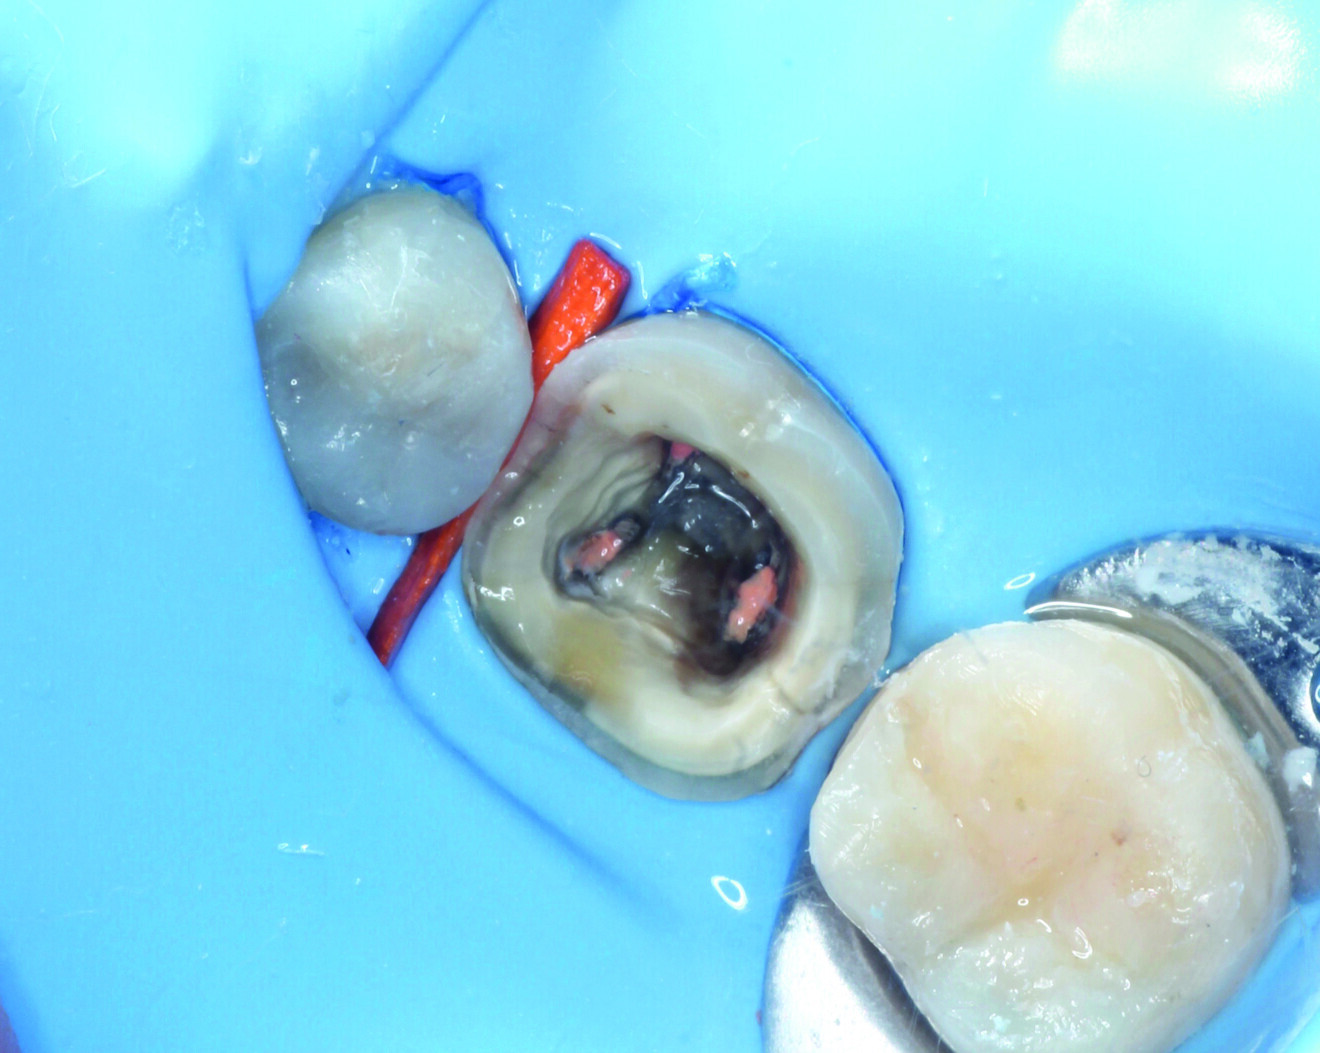

Fig. 4: Building the distal wall to convert the cavity from a Class II to a Class I configuration.

Fig. 5: Completed filling with Grandio.

The direct restoration of tooth #45 used the light-polymerising, nano-hybrid composite Grandio. We rebuilt the distal wall, initially with Grandio, in order to convert the Class II configuration into a Class I cavity design (Fig. 4). This strategy was chosen to make the handling of the proximal and occlusal filling easier. To achieve this, a regular incremental layering technique was used (Fig. 5). Finally, we performed finishing and polishing of the occlusal surface of tooth #45.